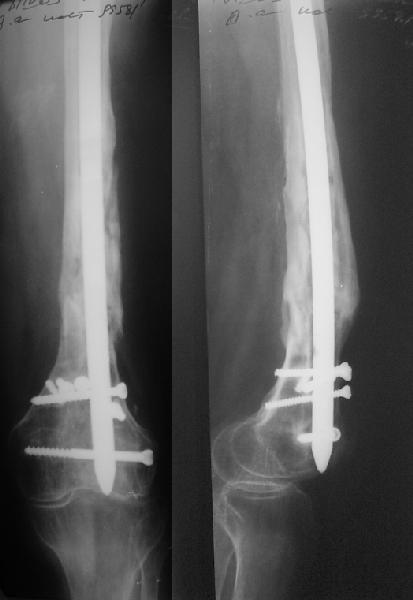

В 2002 г. была у нас больная с ложным суставом бедра и остеомиелитом (как оказалось), после удаления пластины. Гвоздь с блокированием.

Потекло через месяц - открылось 2 свища по старому рубцу от давно удаленной пластины. На фоне гноя раза три завинчивал обратно винты, которые вылезали латерально, прямо через свищ. Потом таки провел дополнительно винты мимо гвоздя, и убрал вверху статический винт. Острый гнойный процесс стих, свищи мыла она дома дважды в день водным хлоргексидином, ходила с возрастающей нагрузкой, а к 10 мес. и свищи закрылись, и срослось. Итоговые снимки от 18 апреля 2003 г. прилагаю.

Рентгенограмы

Не удается отправить первичные снимки. А что скажите по имеющимся?!

Отправитель: А. Миронов 21 Январь 2005, 20:49

Выполненный остосинтез нестабилен. Штифт надо заменить по "размеру" на солидный, дистльно три запирающих винта. Успехов!

Отправитель: Alexander Chelnokov 21 Январь 2005, 21:31

Перелом спиральный, то есть низкоэнергетический, так что со сращением дело обстоит уже неплохо, лишь бы "костоеда" не развилась. Отломки выглядят уже стабилизированными костной мозолью, так что довводить винты, наверно, уже незачем. Разве что при клинической оценке подвижность еще есть - тогда можно для стабилизации наложить простейший аппарат, не опасаясь контакта его элементов с гвоздем, поскольку места в дистальном метафизе оставлено более чем достаточно.

Отправитель: Djoldas Kuldjanov, M.D. 21 Январь 2005, 23:48

С Александром согласен, нет необходимости делать дополнительные усилия для сращения, не большая компрессия аппаратом из двух колец и полная нагрузка доделает работу.

Отправитель: А.Миронов 23 Январь 2005, 11:48

Потекли блокирующие винты.

Удалять их всё равно придётся.

Уже имеется какое-то сращение. А в этих условиях выполнить реостеосинтез гвоздём не дольше, чем "накинуть" аппарат из двух колец. Ходить можно сразу с полной нагрузкой, да и качество жизни пациента без аппарата лучше.